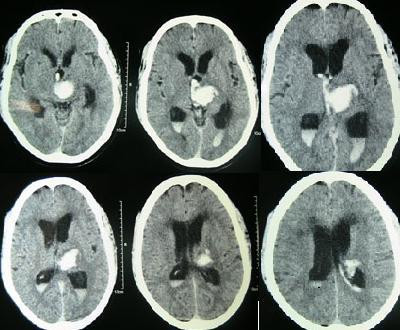

Intracerebral Hemorrhage

An intracerebral hemorrhage is due to brain parenchyma bleeding.

Intracerebral hemorrhage may result from:

- Lenticulostriate vessel rupture

- Aneurysm rupture

The most typical location of the brain involved by intracerebral hemorrhage is the basal ganglia.

Intracerebral hemorrhage hemorrhages may be caused by hypertension.